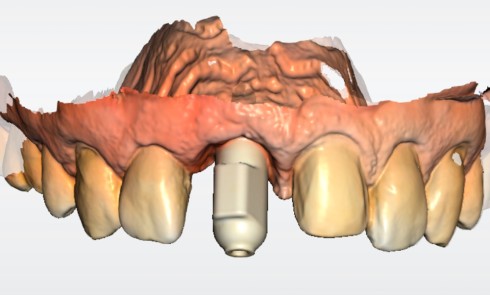

L’implant

- Site 23

- Mis en place il y a 12 ans